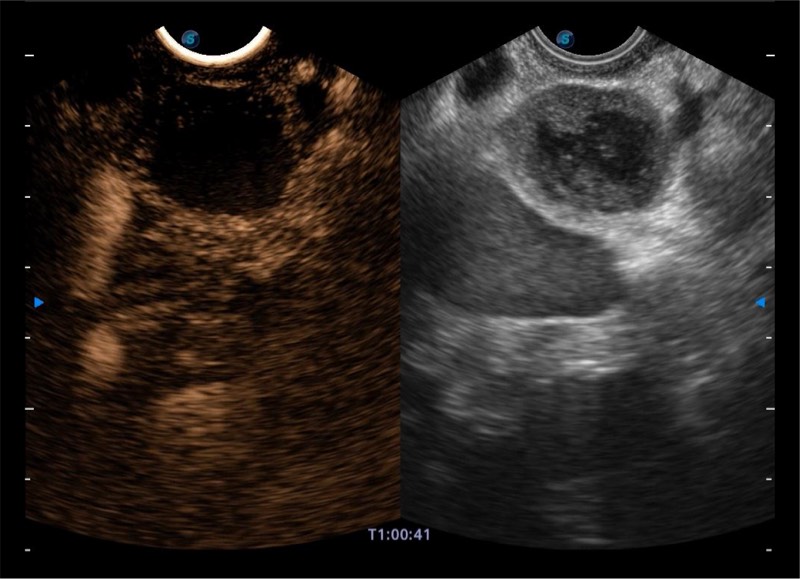

搭载百万级CMOS成像技术

及自主研发凸阵换能器,

可呈现优质的内镜和超声画面

基于二十年的超声技术积累,狗万官方网站提供了最新一代的独立超声主机,在提供高质量图像的同时满足多学科使用。具备常见多普勒技术并提供弹性成像、声学造影等高端影像技术。新一代传感器具有更强的抗干扰能力并减少图像伪影。